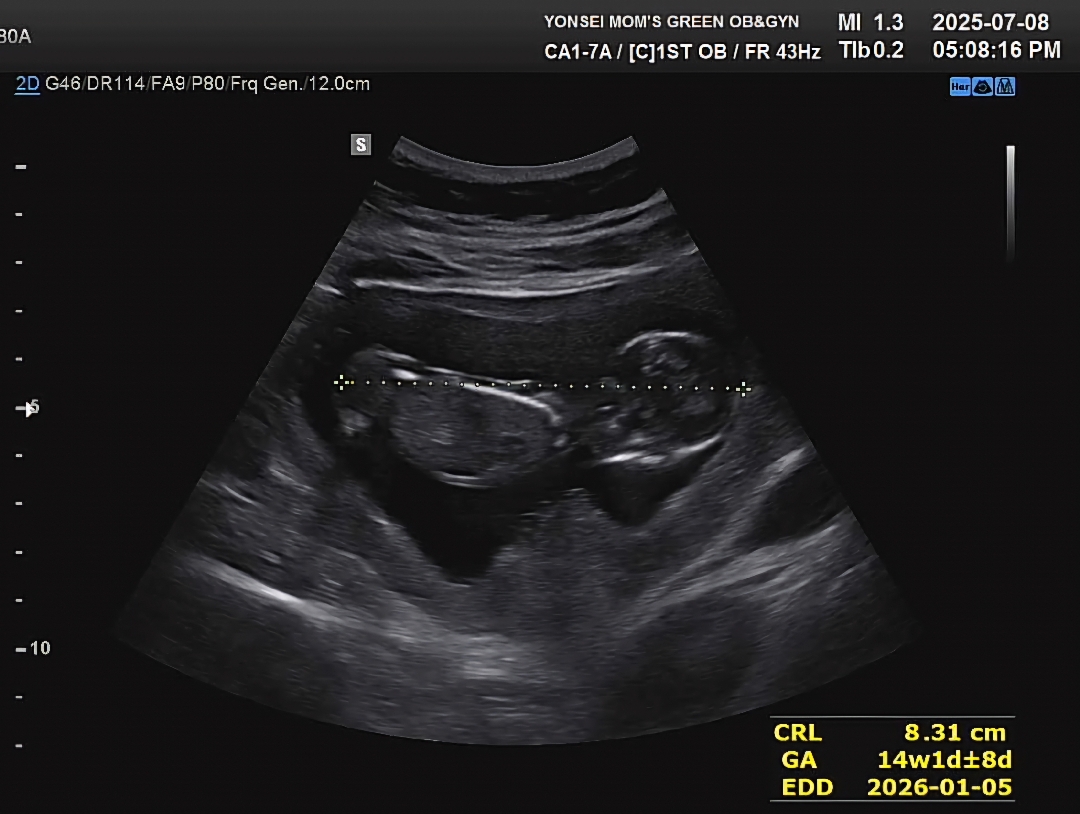

저도 각도법 궁금했는데ㅠㅠ..

왜 엎드려있을까요..? 이걸로도 아들인지 딸인지 구분 가능하실까요??

아들같아요!